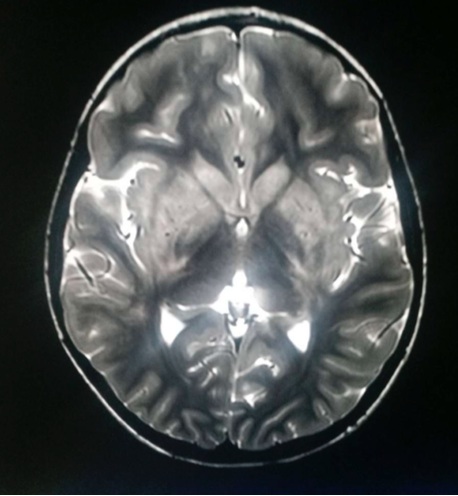

di Emergenza e Accettazione, dove viene riscontrata una leucocitosi neutrofila (26.440/mm3, neutrofili 88,9%) e una adenomesenterite all’ecografia, per cui dopo breve osservazione viene dimessa. Dopo un mese alla sintomatologia si aggiunge febbre (38,5 °C), deviazione del collo, astenia agli arti inferiori e deambulazione incerta, per cui si ricovera. È sofferente, irritabile e presenta rigidità nucale con posizione preferenziale supina. Nel sospetto di meningoencefalite viene eseguita una RMN cranio-encefalo-rachide, che mostra un’alterazione di segnale a carattere flogistico/edemigeno corticale e sottocorticale in sede parietale, caudale occipitale e temporale omolaterale con enhancement leptomeningeo e analoga alterazione dei talami (Figure 1 e 2).